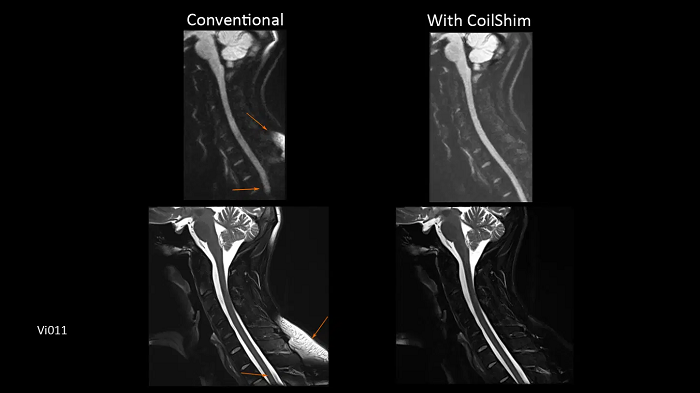

C-spine imaging with and without CoilShim

The groundbreaking CoilShim technology incorporates shim components into the new BioMatrix Head/Neck coils, enabling patient and region-specific shimming for dramatically increased fat saturation and DWI quality.

- BioMatrix Head/Neck 20 (18° tilt)